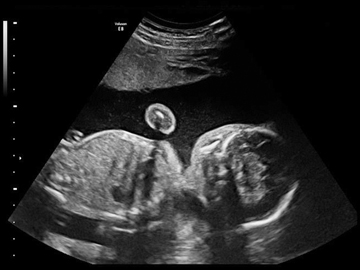

| Скрининговое УЗИ плода + 3D/4D УЗИ (двойня) | 6400 |